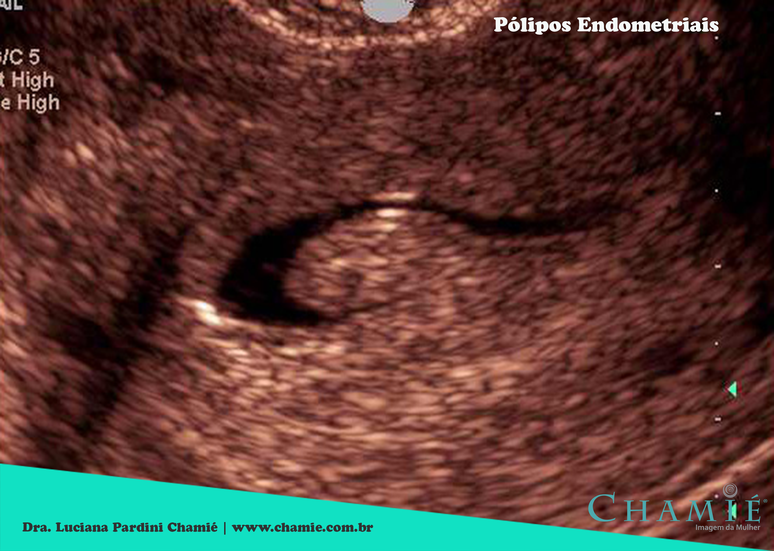

Os pólipos endometriais são formações nodulares ou projeções da mucosa do endométrio (tecido que reveste internamente o útero). Geralmente benignos e nutridos por um eixo vascular, os pólipos são sensíveis ao estímulo do hormônio estrogênio. Podem ser únicos ou múltiplos, e são mais frequentes em mulheres entre 40 e 50 anos. Suas dimensões são variáveis, e sua localização mais comum é no fundo uterino.

Foto: DINO

De acordo com a Dra. Luciana Chamié, especialista em diagnóstico por imagem, o diagnóstico dos pólipos pode ser feito por intermédio de um exame ultrassonográfico transvaginal de rotina. "Há uma ressalta quanto as mulheres que ainda menstruam, o exame deve ser realizado preferencialmente entre o 8º e o 11º dias do ciclo menstrual, já que os pólipos geralmente apresentam um aspecto branco (hiperecogênico) ao exame ultrassonográfico, e podem ser confundidos com o endométrio da segunda fase do ciclo (pós-ovulatória ou secretora). Nesse período, o endométrio conta com um aspecto trilaminar e predominantemente cinza (hipoecogênico), facilitando muito a identificação dos nódulos", explica a médica.

O início do ciclo menstrual também não é um bom período para o diagnóstico dos pólipos, uma vez que o endométrio está fino e pode apresentar um aspecto heterogêneo em decorrência do fluxo intenso. "Para obter imagens mais elucidativas, um exame de histerossonografia pode ser realizado. Neste teste, a injeção de soro fisiológico na cavidade uterina auxilia na visualização do pólipo e da superfície do endométrio. Outro exame que pode ser feito é a histeroscopia, uma espécie de endoscopia do útero", afirma Chamié.